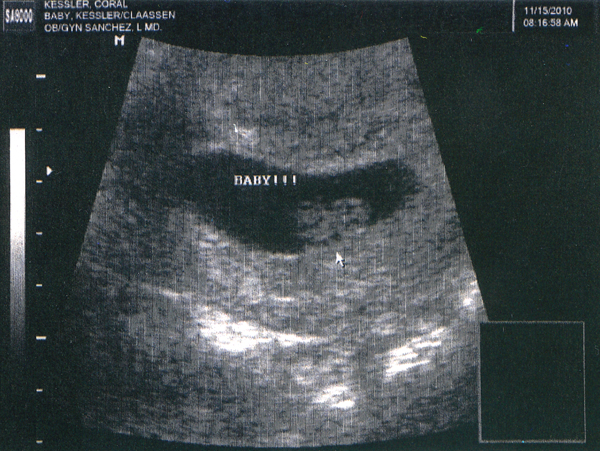

Blob Update: Less Tadpole, More Human

We got to hang out with our little angel today. Of course, he/she has no idea we were watching it twist and turn and punch, but we were stoked on our little hang out session. Aw, look at that profile! Isn’t it a cute little blob? Yes, I’m biased. So what? You know, it looks a lot less like a tadpole and much more like a human now. I might have to stop calling it “blob”. It’s a good thing we don’t own one of those ultrasound machines. It would be hard to not watch it move around all day. Not to mention all the other fun stuff to ultrasound. I’d love to take a look at Pascal’s insides.